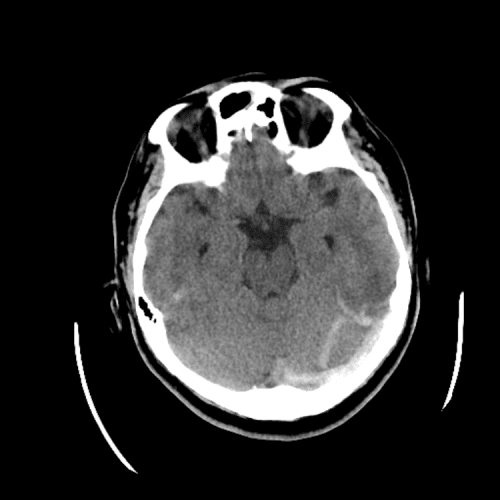

PICA infarct